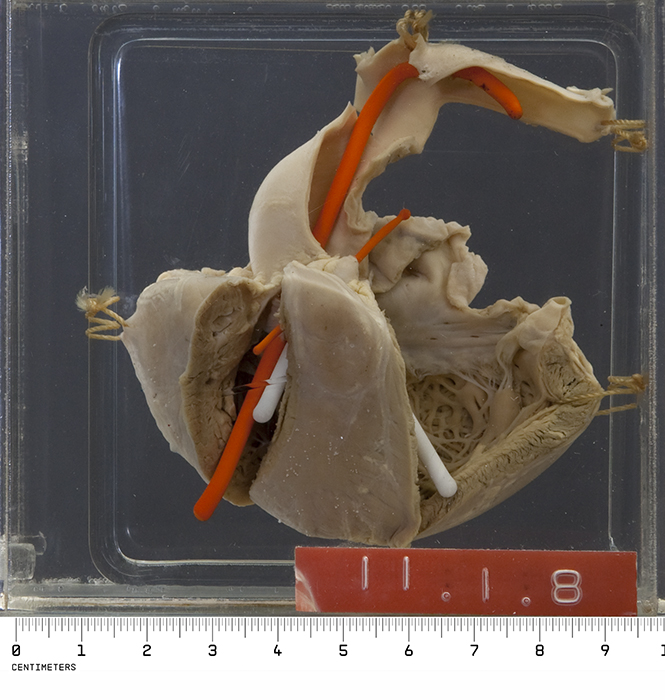

Tetralogy of Fallot (ToF)

Tetralogy of Fallot (ToF) is a congenital cardiovascular anomaly that includes:

- Right ventricular outflow tract stenosis

- Right ventricular hypertrophy

- Ventricular septal defect (VSD)

- An overriding aorta

Early cyanosis is caused by right-to-left shunting, and the degree of stenosis dictates how much shunting and cyanosis is present.